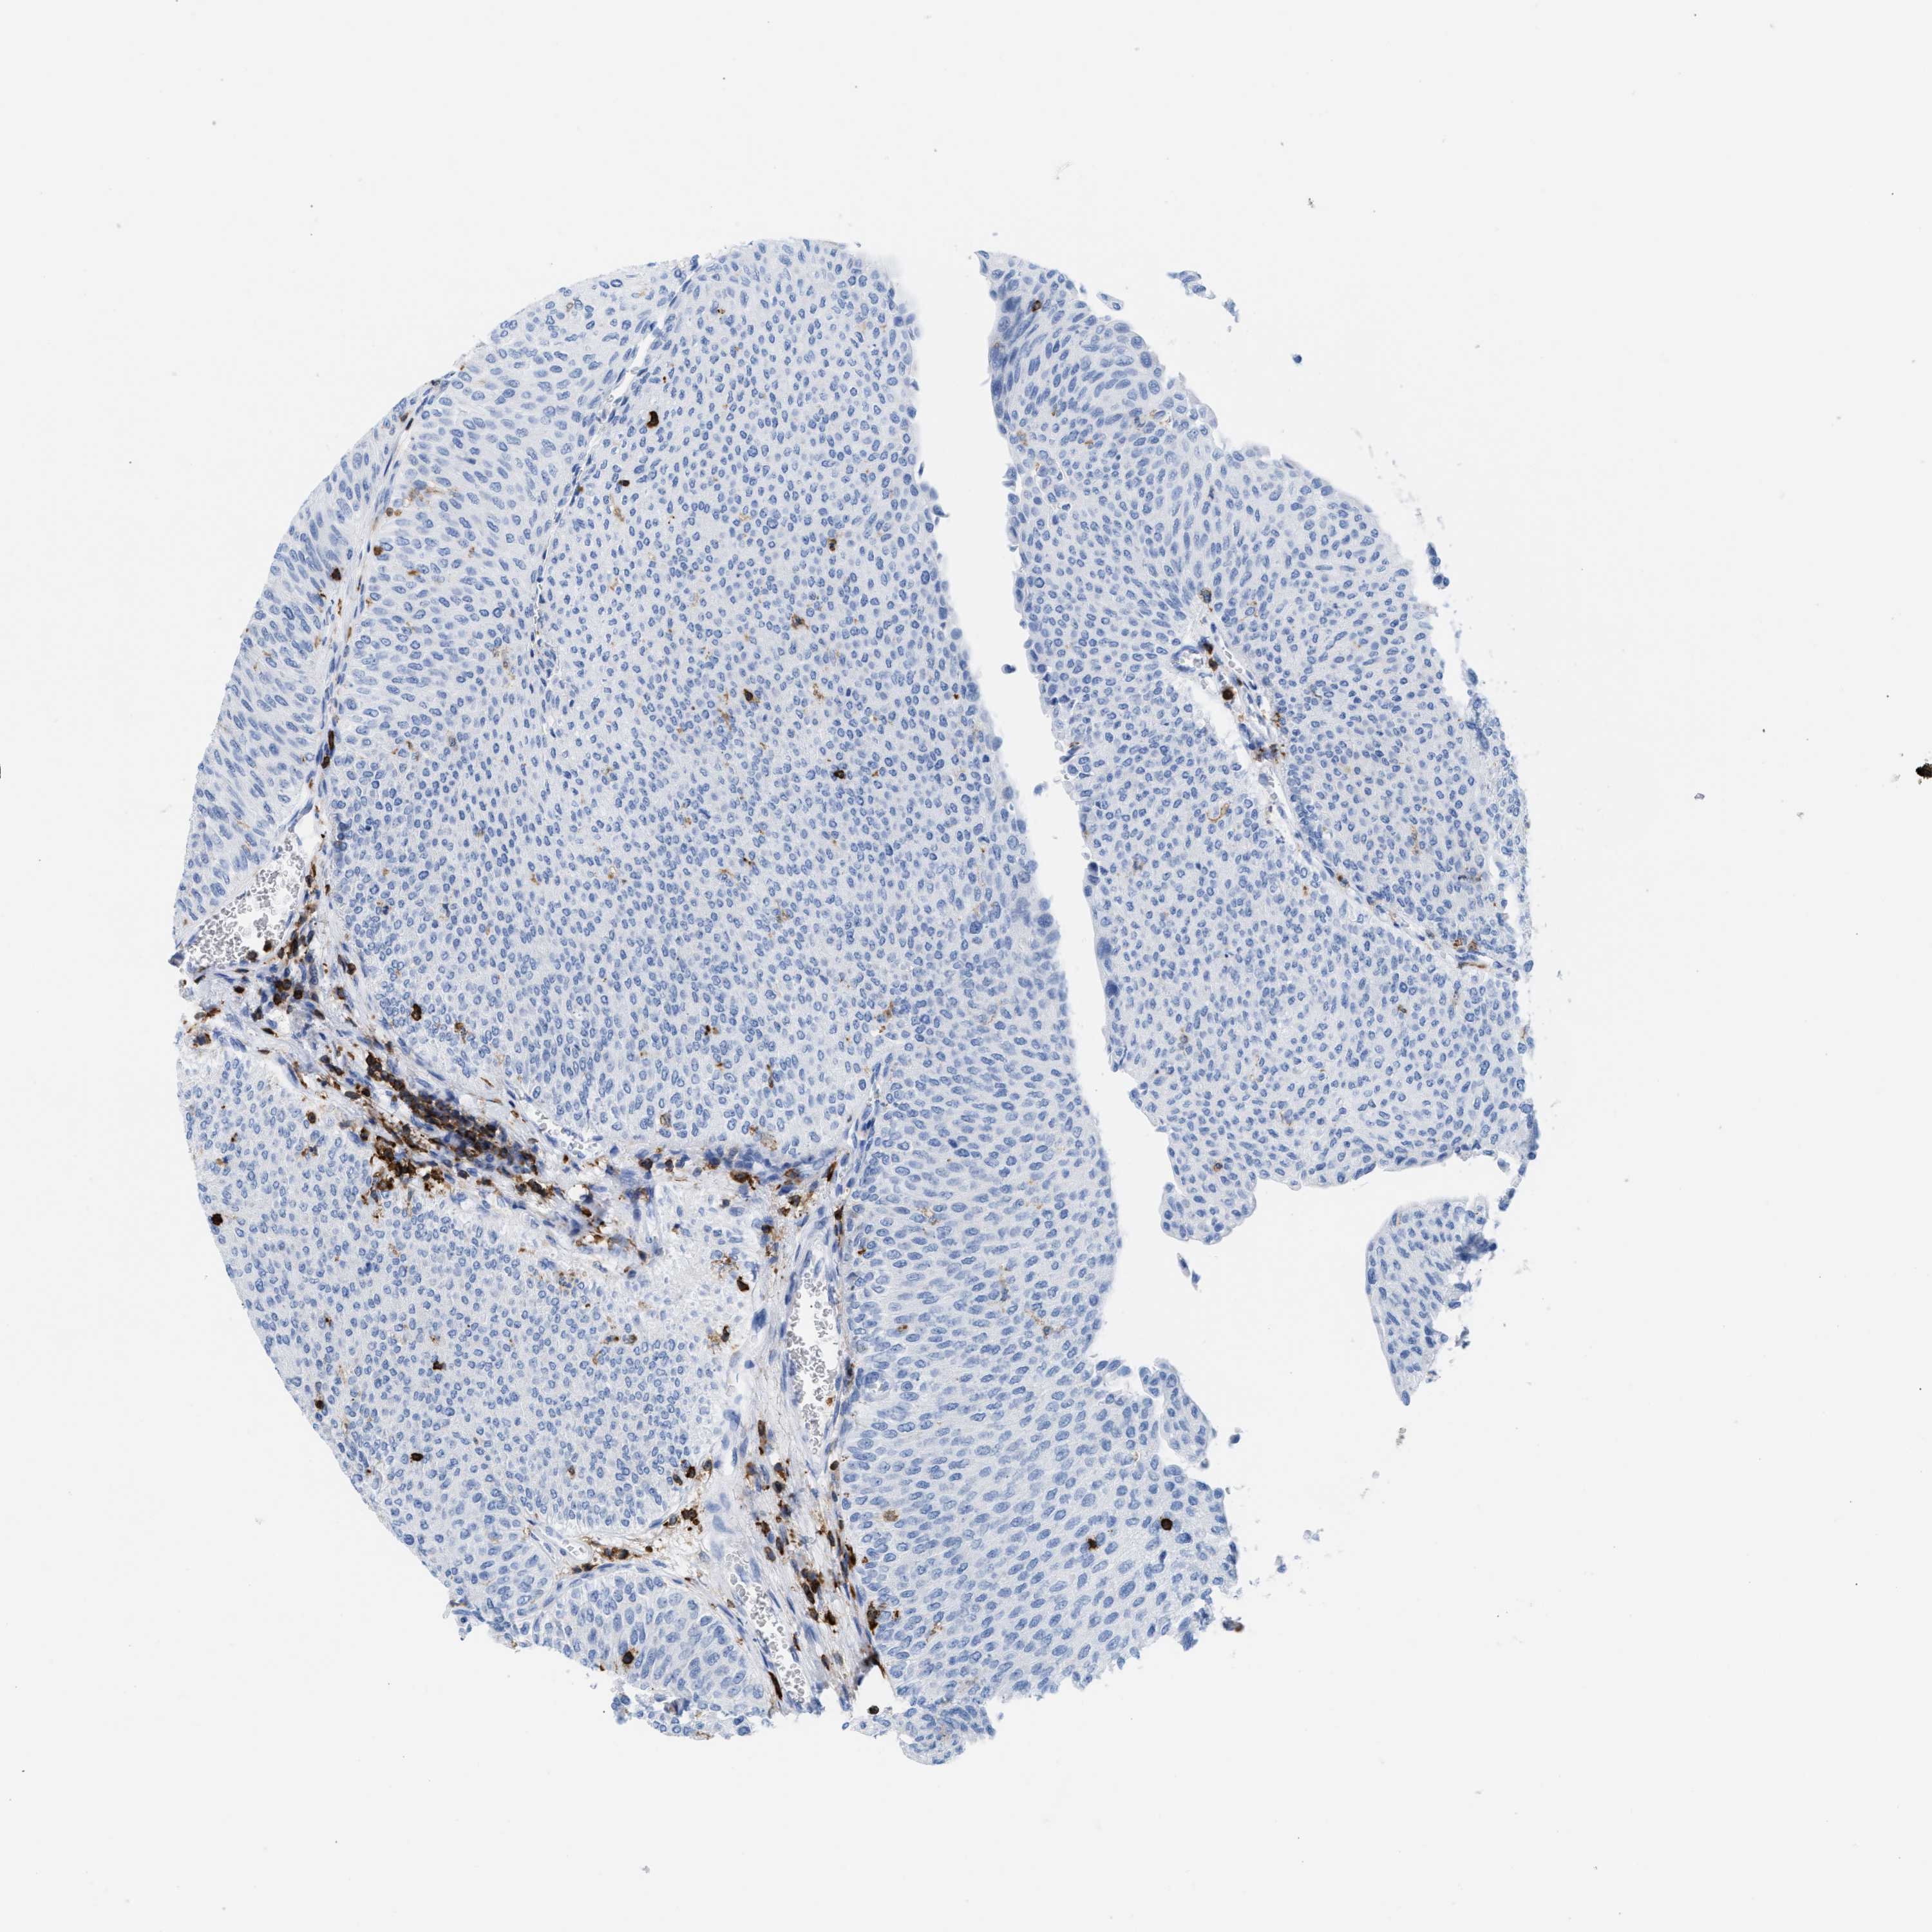

UROTHELIAL CANCER - Protein expressioni

A mouse-over function shows sample information and annotation data. Click on an image to view it in a full screen mode. Samples can be filtered based on level of antibody staining by selecting one or several of the following categories: high, medium, low and not detected. The assay and annotation is described here.

Antibody stainingi

Antibody staining in the annotated cell types in the current human tissue is reported as not detected, low, medium, or high, based on conventional immunohistochemistry profiling in selected tissues. This score is based on the combination of the staining intensity and fraction of stained cells.

Each image is clickable and will lead to virtual microscopy that enables deeper exploration of all samples and also displays staining intensity scores, fraction scores and subcellular localization as well as patient and tissue information for each sample.

Antibody HPA019493

Urothelial carcinoma, Low grade

Urothelial carcinoma, High grade